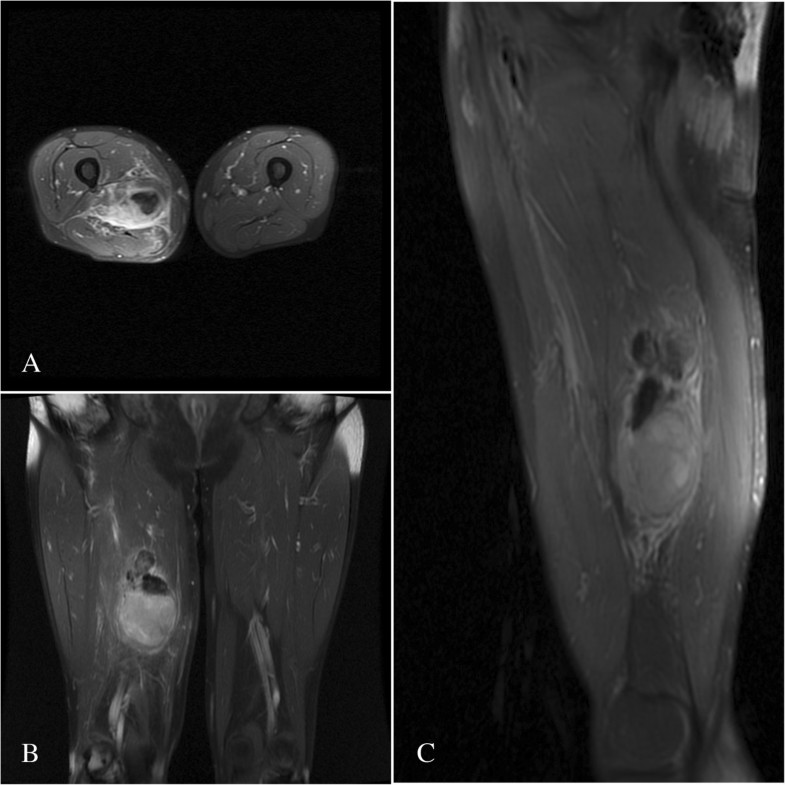

Figure 4 from Normal MR imaging anatomy of the thigh and leg Anatomy Mri Thigh The purpose of this article is twofold: This section of the website will explain how to plan for an mri thigh (upper legs) scans, protocols for mri thigh (upper legs), how to position for. Rectus femoris vastus intermedius vastus intermedius muscle adductor brevis adductor magnus gracilis. Thigh muscles are responsible for allowing normal gait and proper lower extremity function(1). Stanford. Anatomy Mri Thigh.